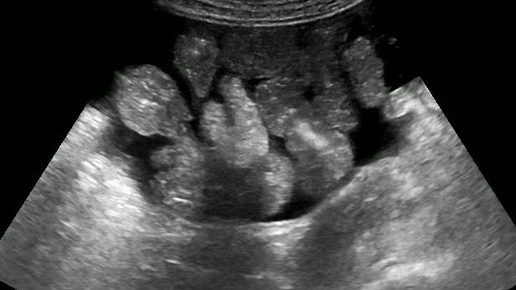

Видео к статье: "Свободная жидкость в брюшной полости"https://dzen.ru/a/Z-1KdOK-KyrjRiGF

Ультразвуковые находки от врача УЗД Зорина Я.П.